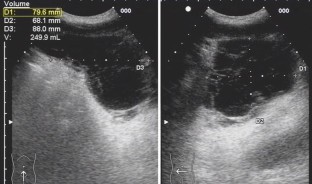

Fig. 2